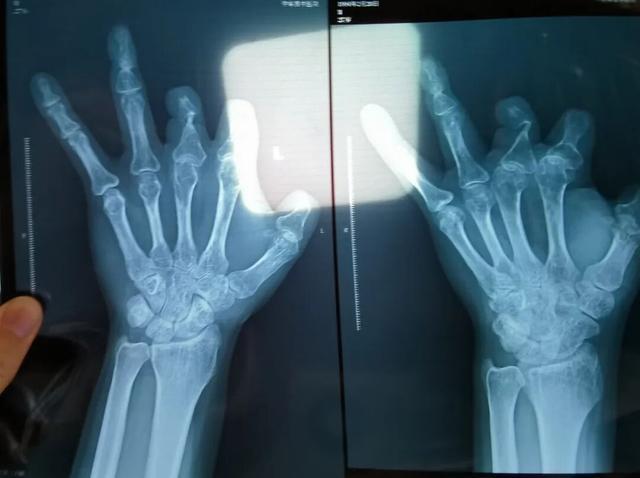

该产品的代理商曾向新京报记者证实,微血管吻合装置为植入型医疗器材,患者拍摄X光片时会有显示。新京报记者获取了一位曾在郑大一附院接受手术、使用了该产品的患者的X光片,其手术部位可见一绿豆大小的光圈。

患者王海森左手拇指关节以上部位被电锯切断,收费单显示术中使用了微血管吻合装置,但X光片中未显示该器械。新京报记者 程亚龙 摄

单价1.68万元,声称在术中植入体内、用于缝合血管的两个环形吻合装置,竟然在王海森的X光片上消失了。

王海森称,他出院约1年后,有人曾找到他说,这个价格昂贵的进口器材,并没有在手术中使用。当时他没有相信,直到2021年12月,经人提醒,王海森在老家开封尉氏县人民医院拍摄了左手X光片,才确认手术部位的确没有微血管吻合装置。2021年12月底,王海森向郑州市公安局二七分局刑侦大队报案。

2021年12月,患者彭先生拍摄的左手X光片,未见收费单据中列出的微血管吻合装置。新京报记者 程亚龙 摄

装置上带有不锈钢针,不可能被人体吸收,唯一的可能就是“手术时其实没有使用”。尽管之前也有其他人向王海森透露过这一点,但直到看到片子前,他一直都不相信。